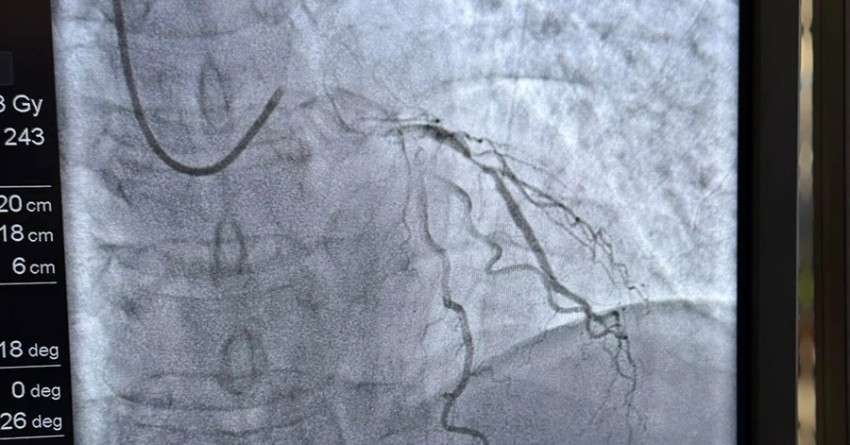

Одним із пацієнтів, який уже скористався цією можливістю, став 53-річний львів’янин Ігор. Чоловік кілька років мав проблеми із серцем, а близько місяця тому почав відчувати задишку та аритмію. Під час візиту до лікарні на консультацію він знепритомнів і був госпіталізований до реанімації. Після стабілізації стану медики провели йому стентування коронарних судин.

Стентування допомагає відновити кровотік у коронарних судинах та зменшити ризик небезпечних ускладнень, зокрема інфаркту. Для реалізації програми держава закупила понад 76 тисяч стент-систем, які використовують для лікування різних уражень коронарних судин. Це дозволяє пацієнтам з ішемічною хворобою серця отримати необхідне втручання без оплати за стент та саму процедуру.

У Клініці серця і судин Університетської лікарні цього року вже виконали понад 40 стентувань коронарних судин. Торік таких втручань було понад 500.